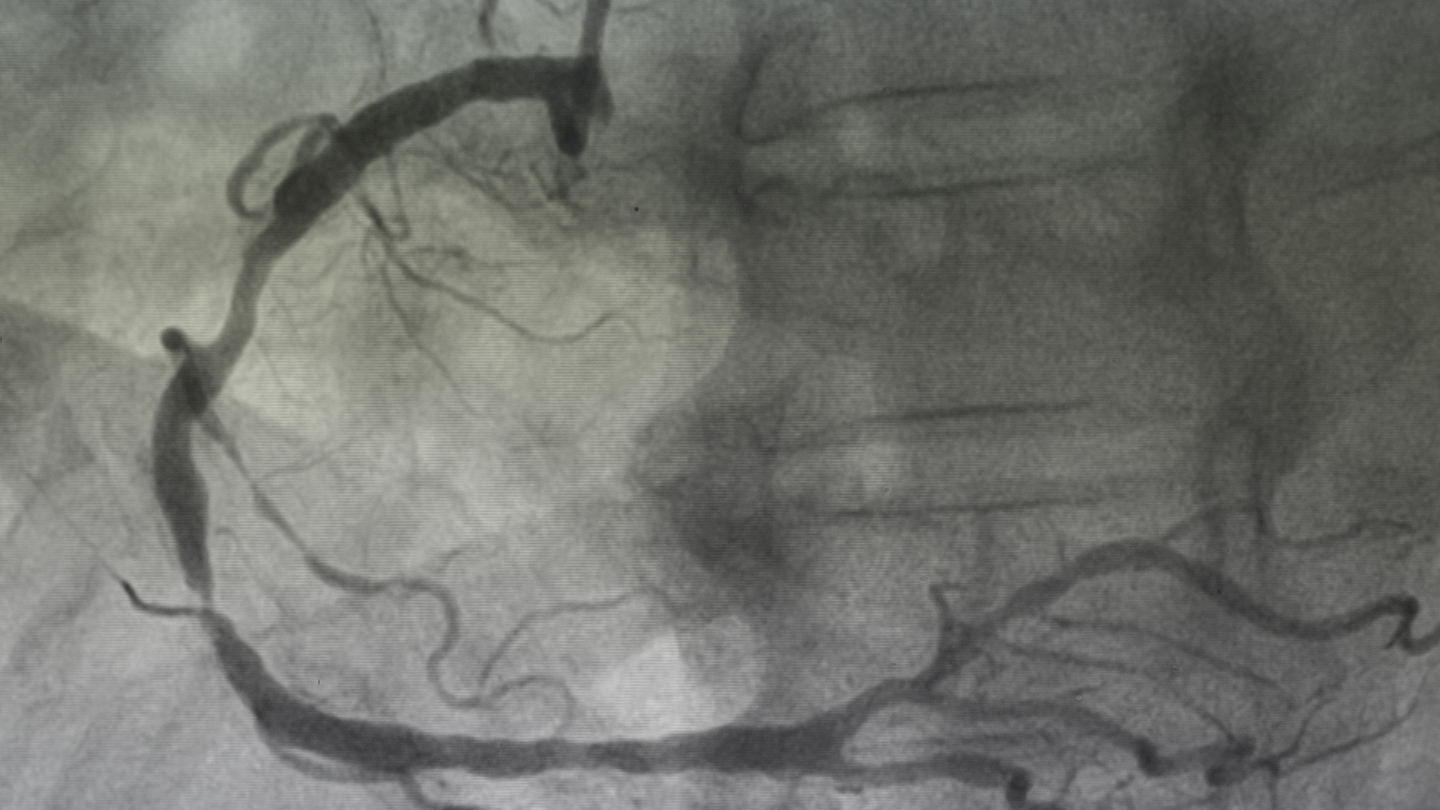

Chụp mạch số hóa xóa nền (DSA - Digital Subtraction Angiography)

Đây là “tiêu chuẩn vàng” để nhìn mạch máu não, được thực hiện bằng cách luồn ống thông từ động mạch đùi lên não và bơm thuốc cản quang.

- Chỉ định: Khi nghi ngờ hẹp/tắc nặng, cần can thiệp đặt stent hoặc lấy huyết khối.

- Ưu điểm: Độ chính xác gần như tuyệt đối.

- Hạn chế: Thủ thuật xâm lấn, có nguy cơ nhỏ (dị ứng thuốc, tổn thương mạch), chỉ làm ở bệnh viện lớn.